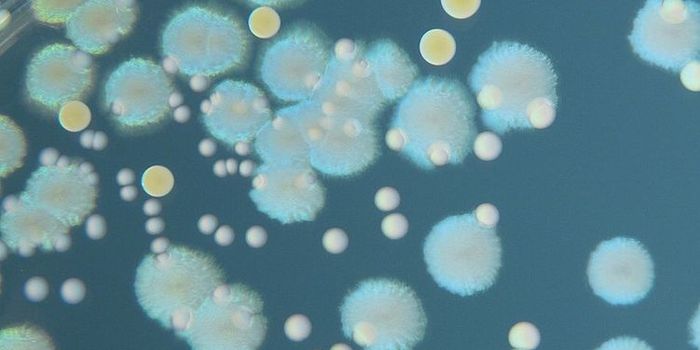

JAN 17, 2023MicrobiologyFungi that can cause lung infections are all over our environment. Recent research has highlighted how much fungal speci ...